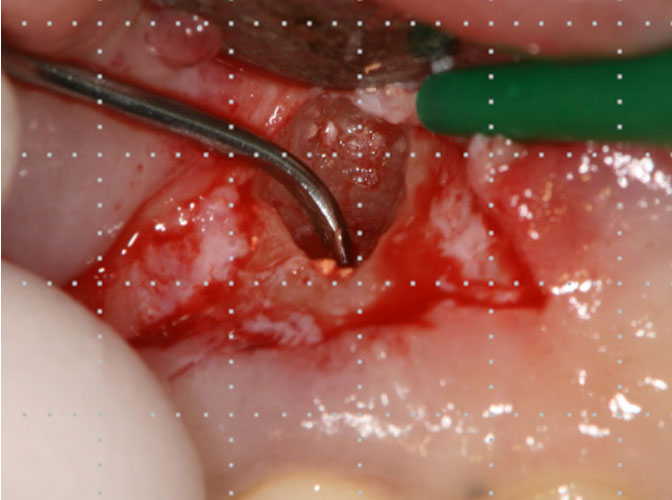

根管治療がうまくいかなかった場合、歯の根の先端に膿がたまることがあります。膿が溜まっている袋が大きいと抜歯になりますが、そうでない場合は外科的な処置で治療できることがあります。歯茎を切開して歯の根を切断し、膿の袋を摘出します。この処置を「歯根端切除術」といいます。

術前

術中

術後